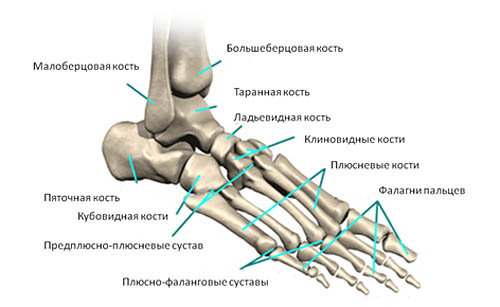

Консолидирующий перелом 5 плюсневой кости с остеопорозом плюсневых костей. Что это:особенности и симптомы

В силу анатомических особенностей, чаще всего остеопороз поражает небольшие кости. Нередки случаи развития остеопороза в мелких костях запястья или предплюсны, в пястных и плюсневых костях. Часто встречается перелом 5 плюсневой кости.

5 плюсневая кость участвует в соединении костей предплюсны с проксимальной фалангой мизинца. Кость расположена латерально, из-за чего значительно возрастает риск ее травмирования в некоторых видах спорта, при беге или же в обычной толпе при неудачном ударе носком ботинка или при подворачивании стопы.

Из-за массивного наличия связок между 5 плюсневой кости и другими, нарушается как структура сводов стопы, так и правильное положение всех плюсневых костей.

Перелом 5 плюсневой кости может развиваться в любой части кости — как в головке, так и в ее теле (для перелома тела плюсневой кости выделен определенный термин — перелом Джонса). Данную травму относят к тяжелым, так как перелом 5 плюсневой кости сопровождается значительным кровотечением и отеком места поражения. Из-за травмы нарушается способность к удержанию равновесия при стоянии — ходьба становится полностью невозможной.